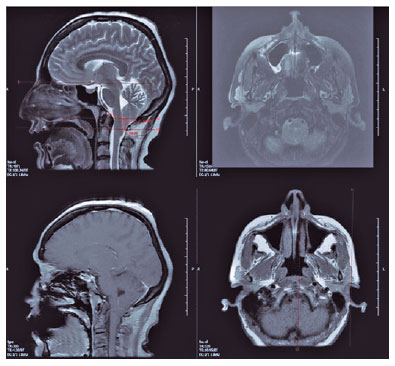

Brain MRI (Figure 2) revealed herniated cerebellar tonsils, approximately 11 mm from the foramen magnum to the inferior. The condition was not accompanied by hydrocephalus, space-occupying lesions, and cerebral venous thromboses. The finding was consistent with CMI.